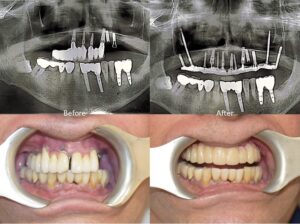

With modern, same-day dental procedures, Dr. Chirag Chamria offers immediate, permanent, fixed restorations that eliminate the need to wear temporary dentures. By using monobloc and the zygomatic implant techniques, even patients with severely damaged bones can receive reliable, functional teeth without delay. When combined with a digitally controlled workflow and efficient laboratory in-house support, the entire procedure minimizes downtime, allowing patients to resume their normal activities with confidence—often the next day.